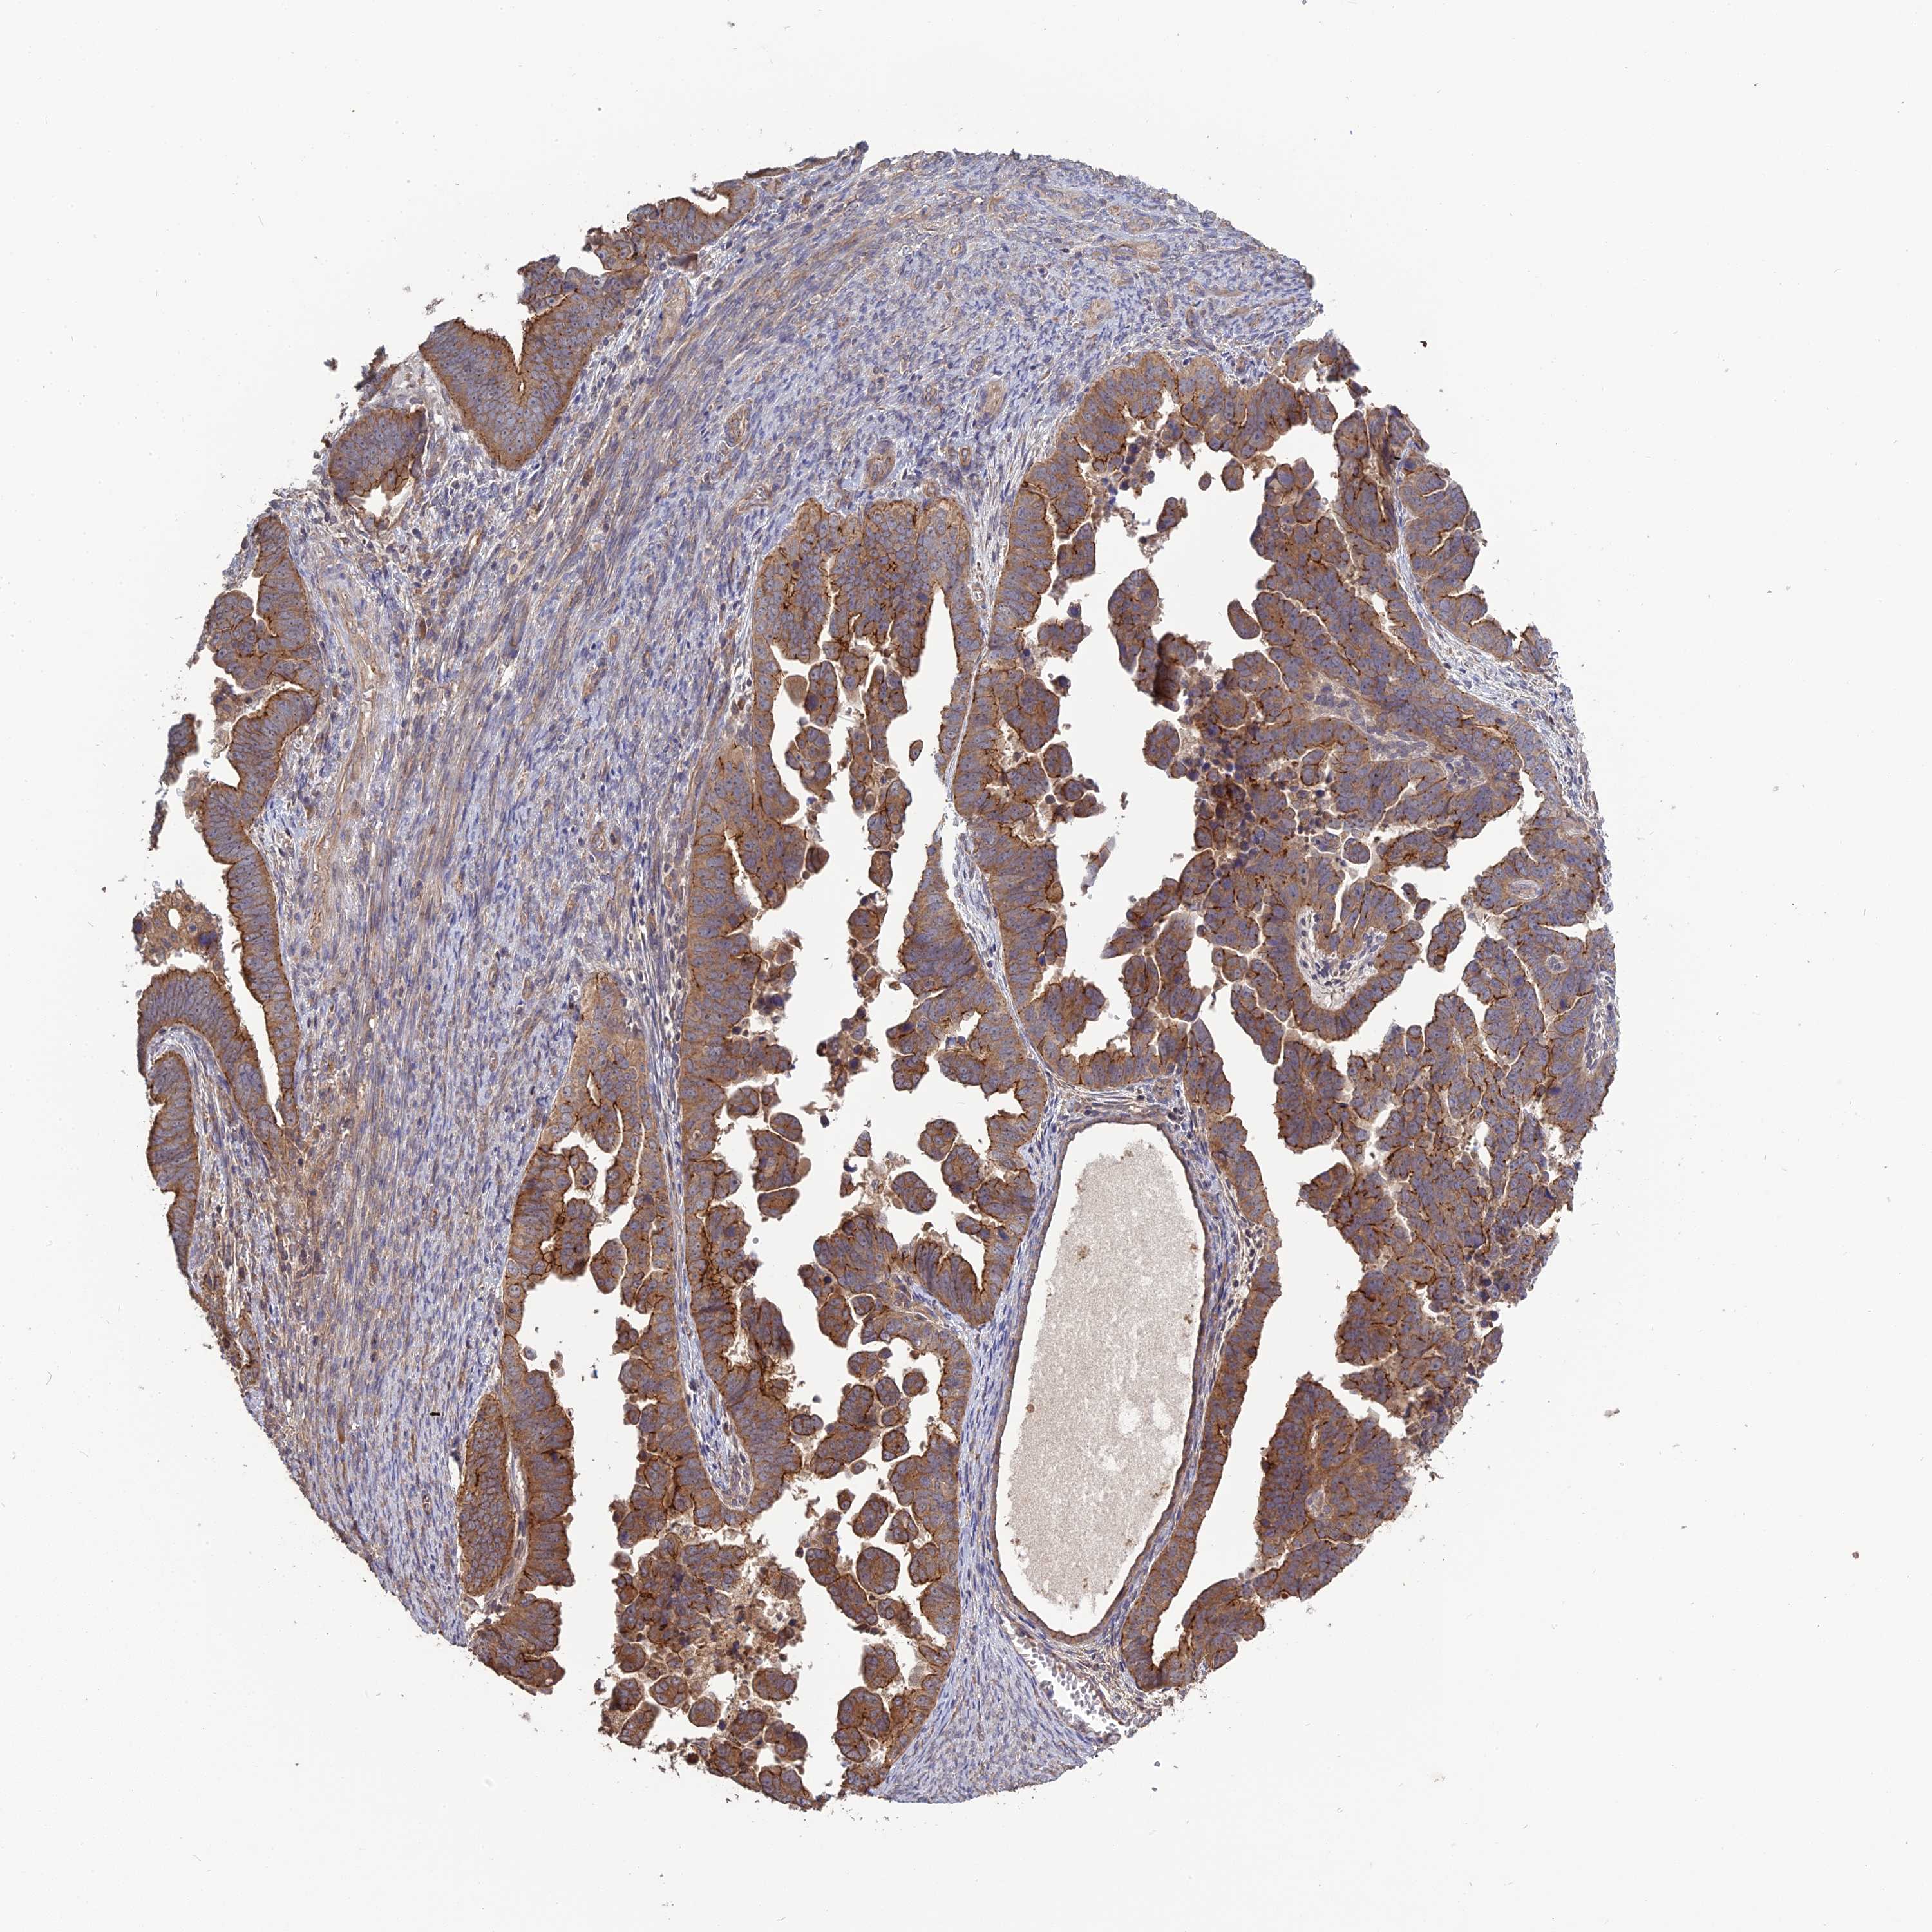

ENDOMETRIAL CANCER - Protein expressioni

A mouse-over function shows sample information and annotation data. Click on an image to view it in a full screen mode. Samples can be filtered based on level of antibody staining by selecting one or several of the following categories: high, medium, low and not detected. The assay and annotation is described here.

Note that samples used for immunohistochemistry by the Human Protein Atlas do not correspond to samples in the TCGA dataset.

Antibody stainingi

Antibody staining in the annotated cell types in the current human tissue is reported as not detected, low, medium, or high, based on conventional immunohistochemistry profiling in selected tissues. This score is based on the combination of the staining intensity and fraction of stained cells.

Each image is clickable and will lead to virtual microscopy that enables deeper exploration of all samples and also displays staining intensity scores, fraction scores and subcellular localization as well as patient and tissue information for each sample.

Antibody HPA042636

Antibody HPA042840

Staining

High

Medium

Low

Not detected

Intensity

Strong

Moderate

Weak

Negative

Quantity

>75%

75%-25%

<25%

None

Location

Nuclear

Cytoplasmic/membranous

Cytoplasmic/membranous,nuclear

Adenocarcinoma, NOS